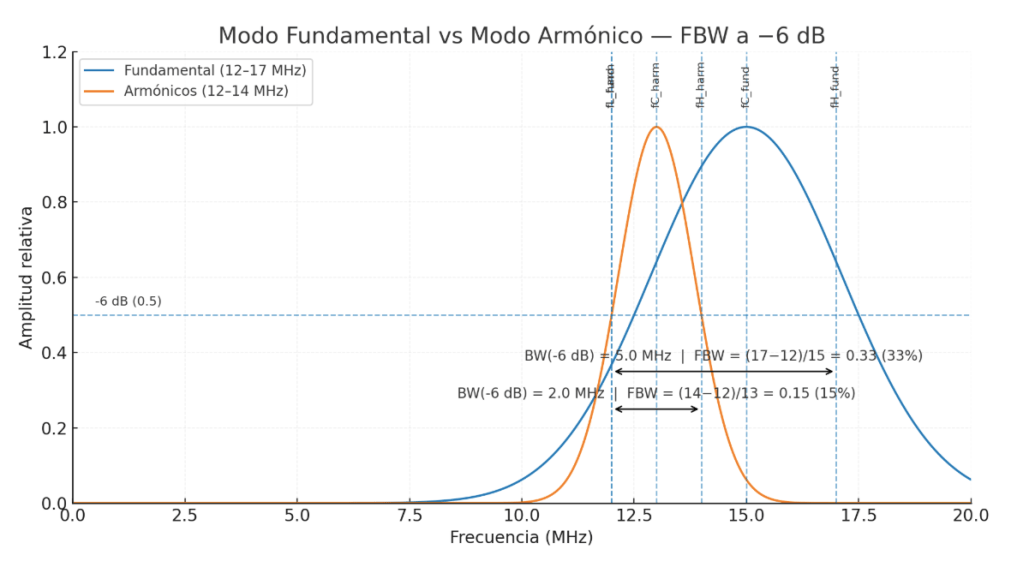

Exploración ecográfica

El estudio ecográfico longitudinal y transversal del compartimento posterior superficial muestra:

- Rotura de la aponeurosis del gastrocnemio medial (GA) con afectación extensa de la aponeurosis libre (FGA).

- Presencia de hematoma intermuscular parcialmente organizado, con septos internos bien definidos que indican fase no aguda del proceso.

- Retracción parcial del vientre muscular del gastrocnemio medial.

- Conservación de la continuidad distal con el tendón de Aquiles.

- Asincronía visible entre gastrocnemio y sóleo durante maniobras dinámicas de dorsiflexión y plantiflexión.

- Microvascularización intramuscular visible en modo Doppler en las fibras retraídas, indicativa de actividad reparativa.

- En la imagen de elastografía de strain, se evidencia menor rigidez en la zona del hematoma, como es esperable, y mayor rigidez en las fibras retraídas, que se comportan de forma más fibrosa y densa en la fase de cicatrización.

- Panoramic View se observa la longitud y extensión de la zona afecta

Clasificación

Según la clasificación ecográfica de Balius-Pedret (2020), la lesión corresponde a un Tipo 4, caracterizado por la afectación combinada de la aponeurosis del gastrocnemio (GA) y de la aponeurosis libre (FGA), con retracción del vientre muscular y hematoma intermuscular.

Este tipo de lesión se asocia a un mayor tiempo de recuperación funcional y riesgo de fibrosis residual o asincronía persistente gastrocnemio-sóleo.

Según reza el informe del radiólogo, el caso es compatible con lesión tipo 4 de Tennis Leg en fase subaguda, entre otros datos.